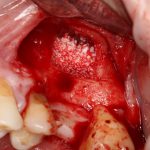

Вот клиническая картина через 4 месяца после ранее проведенной имплантации с остеопластикой:

Как видишь, коллеги из недалекой дружественной страны не осилили снятие швов. Мне это не нравится, хотя и объясняет, почему люди готовы ехать за тыщи километров ради 20-минутной операции удаления зуба мудрости.

Ну хорошо. Швы сняли. Делаем разрез. Обрати внимание, что после всех проведенных операций у нас остается очень небольшой по ширине слой жевательной слизистой оболочки:

Устанавливаем формирователи десневой манжеты. Сегодня я называю эту процедуру не менее важной, чем любой другой этап имплантологического лечения:

И швы. Просто швы. Никаких дополнительных процедур.

Если честно, то сейчас бы я использовал другой шовный материал и другой тип швов. Одно неизменно, — и я об этом много раз говорил, — самая широкая часть формирователя десны должна находиться на уровне десны. Так, чтобы эффективно отрабатывать т. н. «биологическую ширину».